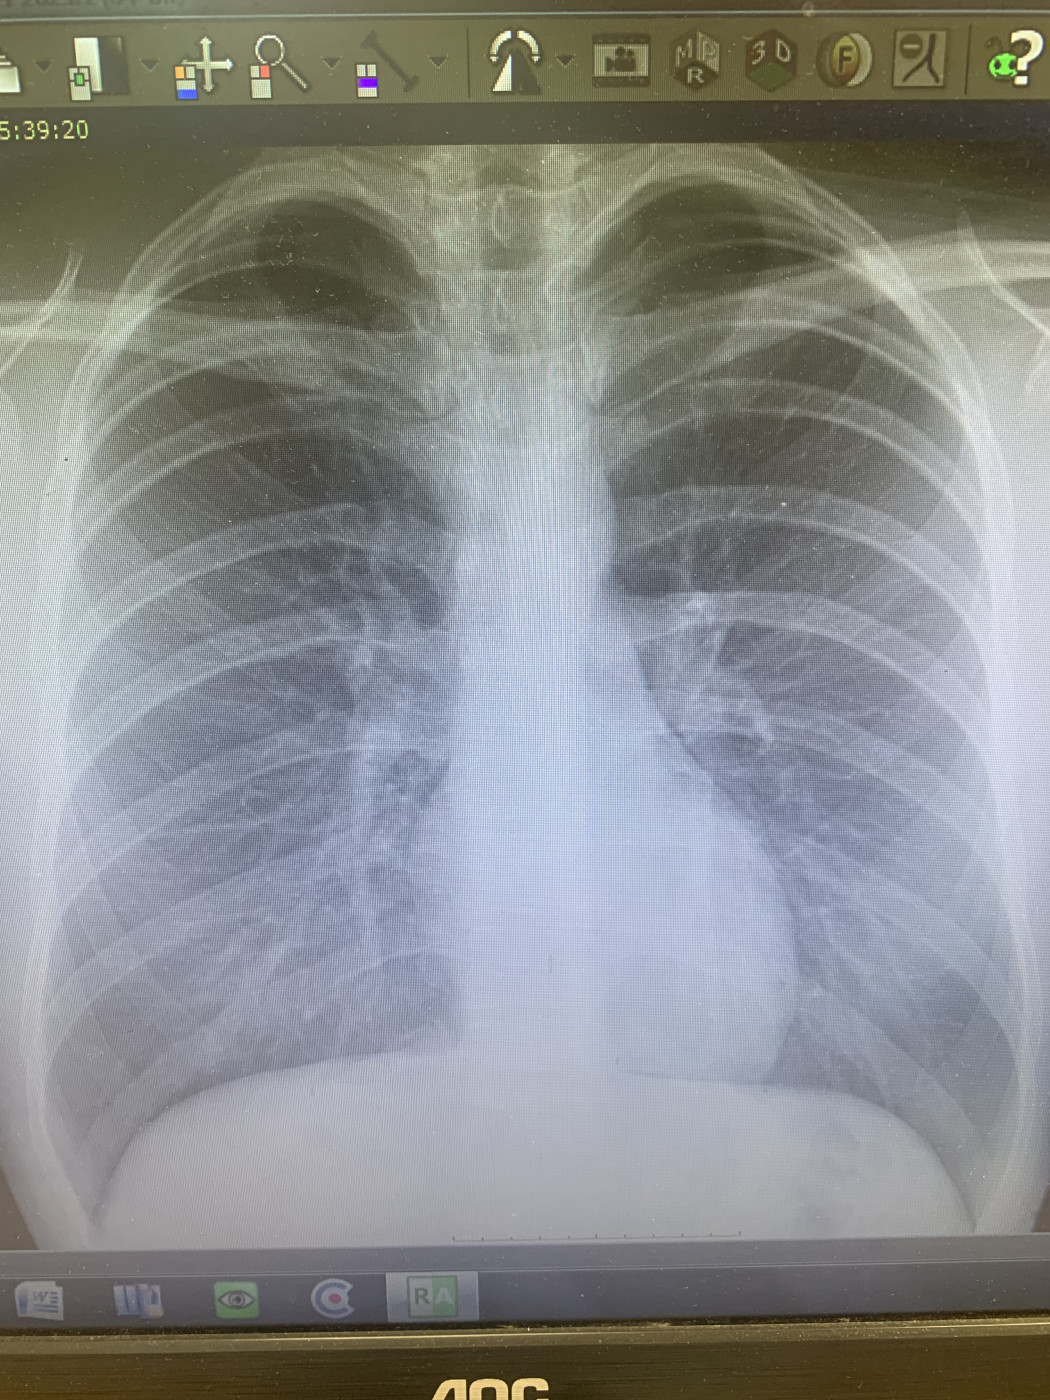

Закрытая травма грудной клетки   1 ответ

Занимался на брусьях, и ребра будто в перед вышли. Как слез, стало норм, но болит в груди по середине. Сходил в больницу, сделали ренген, сказали, вроде ничего не увидели. Выписали пить Немисил и растирать мазь в месте, где болит. Хотелось бы еще раз убедиться, что всё нормально.

7 авг 2025 00:01